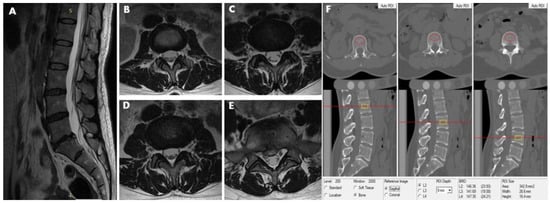

2.5. Lumbar Scanning by MRI

2.6. Definition of Lumbar Intervertebral Disc Herniation